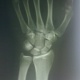

мне видится перелом ладьевидной кости, или у Вас вопрос в хронологии?

Правильно видится.Вопросов нет, просто народ заскучал, вот подкинула пищу для размышлений, а Вы уж сразу и увидели.

для кистевого сустава это перелом тяжелый, срастается тяжело, ложный сустав образуется часто, артрозище возникает, функция нарушается.

Все зависти от локализации перелома,здесь перелом ближе к основанию бугорка ладьевидной кости, что более благоприятно в плане сращения...если тела - то весьма и весьма неблагоприятно...

+1) кровообращение там "поскудное"

Поэтому в нормальных странах переломы ладьевидной кости стараются оперировать первые 2 часа...